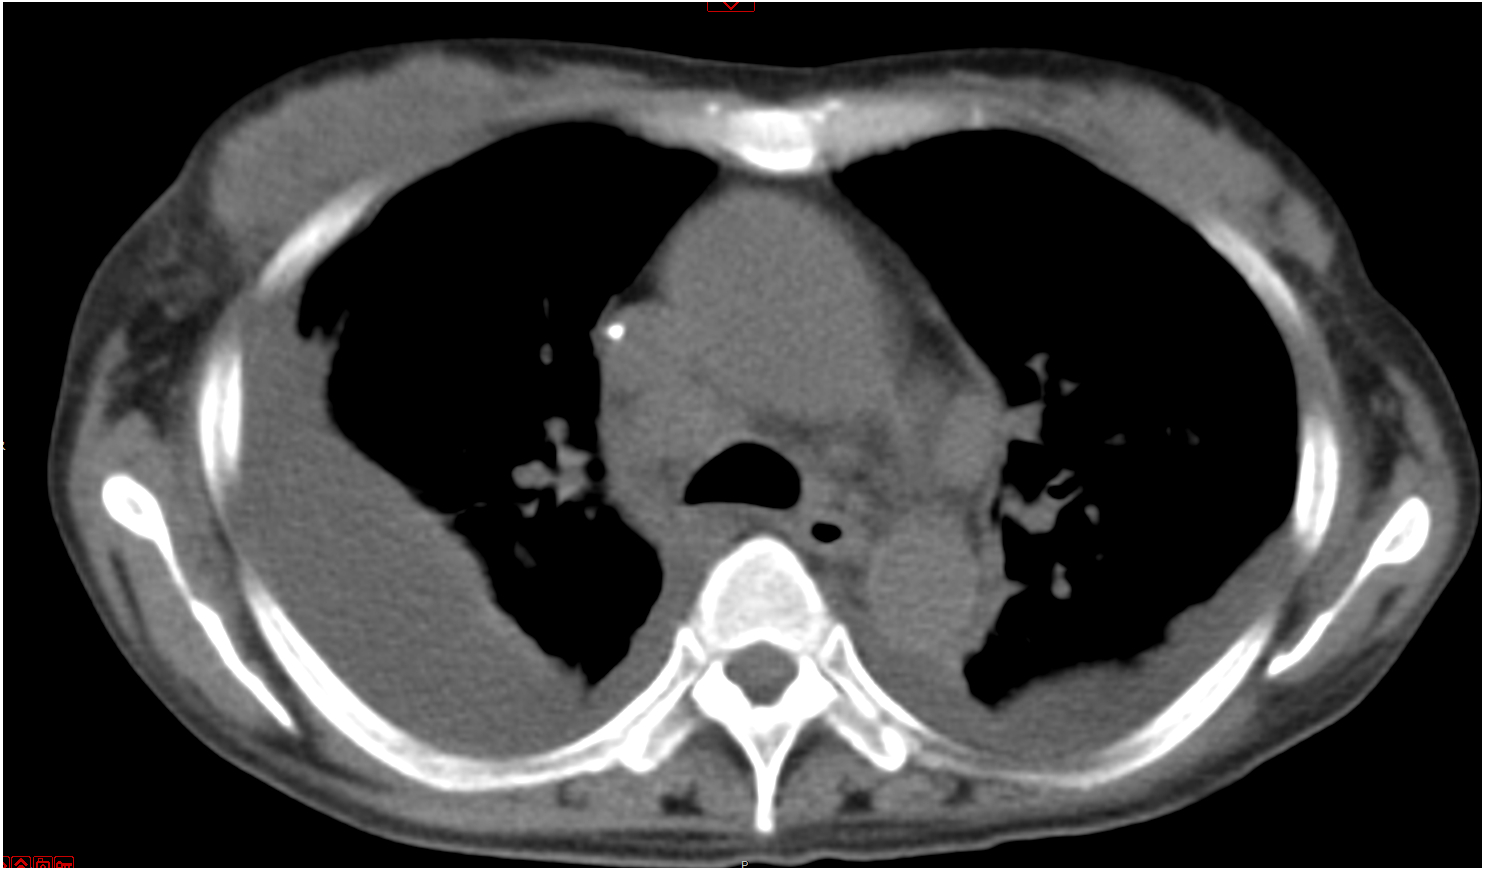

患者于2019-06-17因发热及头痛等不适来本院诊治。查体:体温38.5℃, 心率96次/min,呼吸20次/min,血压132/92 mmHg(1 mmHg=0.133 kPa)。结合症状及既往就诊经历,诊断考虑:发热查因;肺门淋巴结肿大。鉴别诊断:肺结核、淋巴瘤、结节病。同时患者外周血白细胞(WBC)及降钙素原(PCT)升高,不排除细菌感染, 予莫西沙星400 mg治疗5 d, 并在应用抗生素前留取病原学标本。期间行经气管镜超声引导针吸活检术(endobronchial ultrasound-guided transbronchial needlle aspiration, EBUS-TBNA),但无阳性结果。入院后所行的PET-CT提示肿大淋巴结考虑淋巴瘤。双肺小结节,考虑炎性肉芽肿。骨穿无异常结果, 以“肉芽肿(纵膈淋巴结)”为主要诊断出院。图 1为入院后两次胸部平片影像检查结果,可见右肺门影增浓。

| A:2019-07-15检查;B:2019-08-27检查 图 1 CT检查示右肺门影改变 |